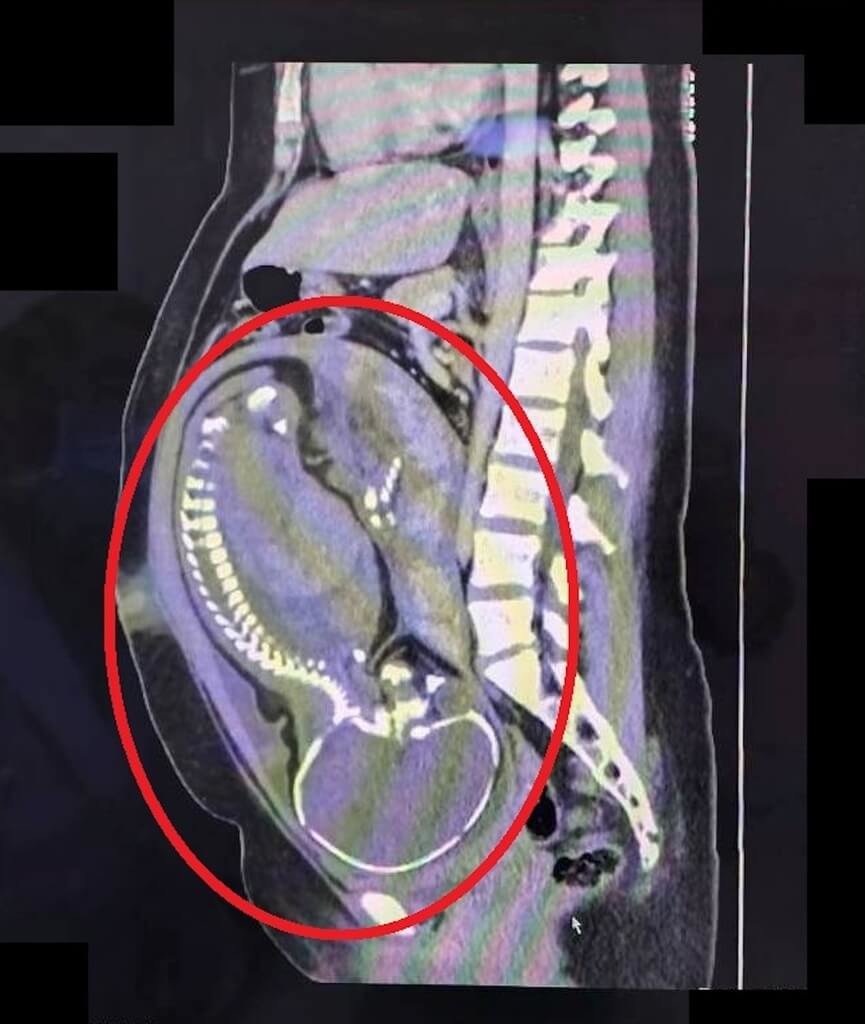

然而腹部觸診時發現,孕婦右下腹有明顯壓痛及反彈痛,高度懷疑是急性盲腸炎,當下立即安排腹部電腦斷層檢查,並會診一般外科主任劉信誠共同評估,經跨科團隊討論並與孕婦及家屬溝通後,決定執行緊急剖腹生產併盲腸切除手術。

林敬旺說,手術中發現盲腸已嚴重腫脹化膿,瀕臨破裂邊緣,腹腔內更已有約100毫升的膿樣腹水,情況危急,所幸醫療團隊妥善保護手術傷口,避免污染的情況下,順利接生寶寶,同時完成盲腸切除手術。產婦順利產下男嬰,術後接受抗生素治療,恢復良好、平安出院。